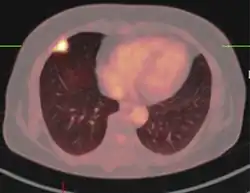

PET scan

If there is an intermediate risk of malignancy, further imaging with positron emission tomography (PET scan) is appropriate (if available). It can be done simultaneously as a CT scan in the form of PET-CT. Around 95% of patients with a malignant nodule will have an abnormal PET scan, while around 78% of patients with a benign nodule will look normal on PET (this is the test sensitivity and specificity).[15] Thus, an abnormal PET scan will reliably pick up cancer, but several other types of nodules (inflammatory or infectious, for example) will also show up on a PET scan. If the nodule has a diameter of less than one centimeter, PET scans are often avoided because of an increased risk of falsely normal results.[15][16][17] Cancerous lesions usually have a high metabolism on PET, as demonstrated by their high uptake of FDG (a radioactive sugar).

-

PET-CT of a tuberculoma.